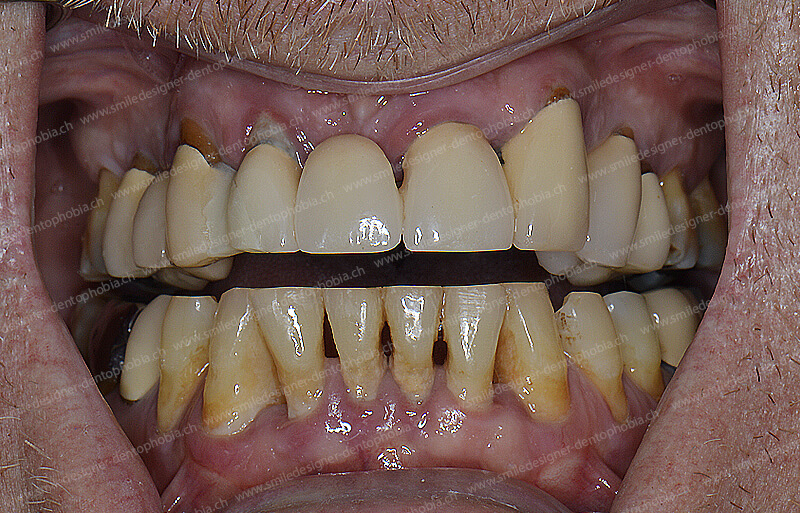

Cas clinique « GOLD STANDARD MCI » mandibulaire : Bridge implanto-porté sans extension postérieure (ALL ON 8). Version définitive du bridge avec un cosmétique en céramique.

traitement

Cas clinique « DAMAGE CONTROL MCI » mandibulaire : Bridge implanto-porté avec extensions postérieures (ALL ON 6). Version définitive du bridge avec un cosmétique en céramique.

Cas clinique « DAMAGE CONTROL MCI » mandibulaire : Bridge implanto-porté avec extensions postérieures (ALL ON 8). Version définitive du bridge avec un cosmétique en céramique.